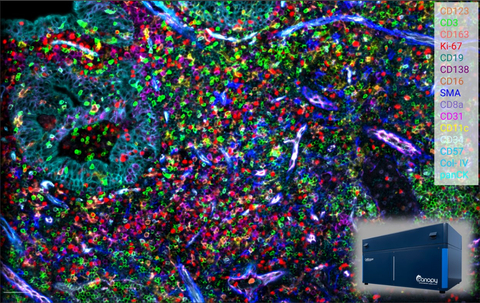

Human FFPE tonsil, 48-plex proteomics assay captured on the CellScape Spatial Proteomics Instrument (inset) using EpicIF technology (Photo: Business Wire)